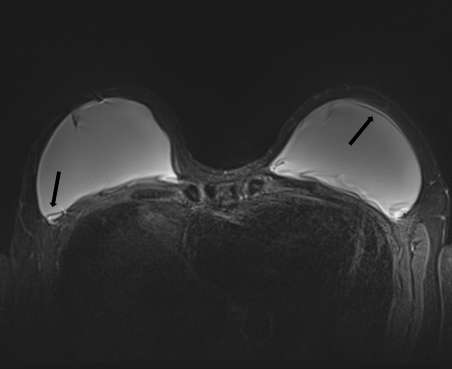

Radial Fold

Radial folds are normal invaginations of the outer shell and can mimic intracapsular ruptures. They are seen as hypointense lines that extend from the periphery and are perpendicular in orientation to the implant capsule (Figure 7). Radial folds can appear as simple or complex folding patterns but are continuous when traced in different imaging planes. Considered a normal variant, radial folds are most commonly caused by capsular contracture9.

Figure 7: T2-weightedfat-saturated image demonstrates normal radial fold extending from the surface of the implant (blackarrows).

Figure 7: T2-weighted fat-saturated image demonstrates normal radial fold extending from the surface of the implant (black arrows).